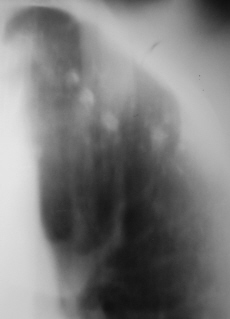

На фрагментах рентгенограмм (иллюстрации 3, 4), в прямой стандартной проекции слева под ключицей определяются полиморфные, различных размеров очаги.